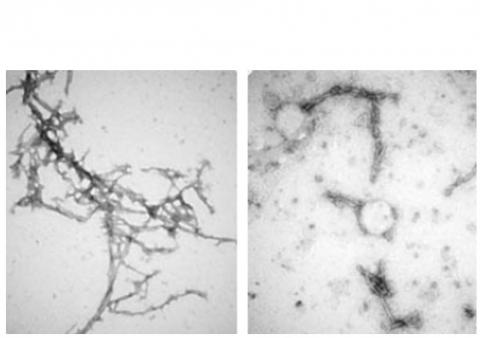

L'étude : les chercheurs de la Johns Hopkins ont développé un nanocorps bien particulier : capable de traverser la membrane extérieure des cellules cérébrales et de démêler les amas de protéines alpha-synucléine qui causent la maladie de Parkinson- mais aussi la démence à corps de Lewy et d'autres troubles neurocognitifs causés par la protéine. On sait aujourd’hui, grâce aux recherches menées sur l’axe intestin-cerveau, que ces amas d'alpha-synucléine peuvent se propager de l'intestin ou du nez au cerveau, favorisant ainsi la progression de la maladie.

PFFNB2 parvient à gommer les amas d'alpha-synucléine tout en épargnant les molécules monomères

d'alpha-synucléine qui ne sont pas nocives et peuvent avoir des fonctions importantes dans les cellules cérébrales ;

- des tests chez la souris modèle de Parkinson montrent que PFFNB2 ne peut pas empêcher l'alpha-synucléine de s'accumuler sous forme d’amas, mais peut en revanche perturber et déstabiliser la structure des amas existants ;